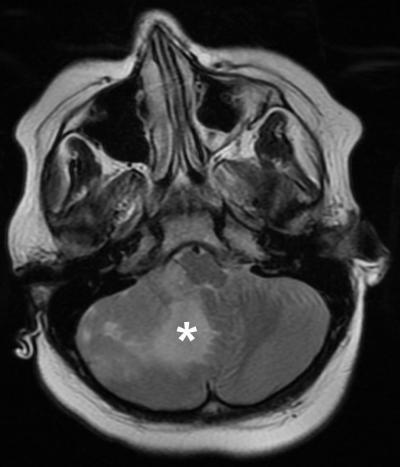

image: A test run of the personalized drug screen was completed using a brain tumor from an 8-year-old boy newly diagnosed with metastatic medulloblastoma. An information package about his tumor, including subtype and drug screening results, identified several drugs that may be effective for his tumor and was reviewed by doctors on a molecular tumor board—demonstrating the feasibility of the method to guide patient care.

To confirm that this approach could be used in the real world, the scientists completed a "test run" using a brain tumor removed from an 8-year-old boy newly diagnosed with metastatic medulloblastoma. A personalized drug screen identified several drugs that may work for his tumor type, and the results were reviewed by a molecular tumor board--a panel of physicians and scientists who work together to discuss treatment options. Although per protocol, the child continued with standard-of-care treatment, the results showed that a personalized treatment plan could have been created in time to guide care decisions.